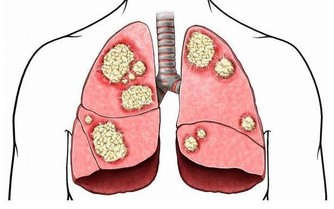

抽菸的人,氣管炎,肺氣腫,肺心病,最後肺癌,這是死亡三部曲。